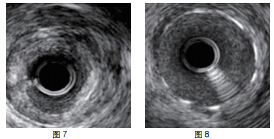

患者RCA为完全闭塞病变,用6F.EBU 3.5导引导管经股动脉对侧造影显示间隔支到RCA远端的侧枝循环,如正向无法开通右冠状动脉可改逆向开通。用JR6F-4导引导管两条pilot-50导引导丝在微导管支持下,用平行导丝技术通过闭塞病变(图3)。分别用Sprinter 1.5 mm×15 mm和2.5 mm×15 mm球囊扩张后RCA开口出现严重夹层,在RCA近端置入Partner 3.0 mm×36 mm支架(图4)。但支架远端仍有严重狭窄,IVUS证实RCA全程弥漫病变,用原2.5 mm球囊扩张后支架远端后,支架远端出现螺旋夹层。拟通过近端支架置入另一Partner 2.75 mm×36 mm支架,但支架无法通过近端支架,头端卡在第一个支架内,在反复用力推送过程中导引导管、导丝自RCA中脱出、将支架球囊弹出,支架球囊撤出体外后发现支架已脱落。透视RCA开口至桡动脉全程,及导引导管内,未发现脱落支架。迅速将原JR4导引导管到位,置BMW导丝到RCA远端,保证RCA开通(图5),IVUS证实导丝全程在真腔内。用原2.5 mm球囊扩张RCA远端以便器械通过(图6)。血管内超声检查提示RCA中段螺旋夹层,撕裂深及血管外膜(图7)。右冠近端支架膨胀、贴壁良好(图8)。将超声导管回撤至右冠状动脉开口处,可见脱落支架卡在右冠状动脉近端支架开口处(图9)。拟取出支架,为预防取出支架过程中RCA急性闭塞,在RCA远端置入BuMA 2.5 mm×30 mm和3.0 mm×30 mm支架,近端支架和原RCA开口处支架未连接(图10)。将Snare圈套器经原作为对侧造影的6F.EBU 3.5导引导管伸出(图11),调整位置,将脱落的支架套住。同时将RCA内的导丝保留,RCA近端支架内预置一3.0 mm×10 mm高压球囊,以保护在取出脱落支架时RCA开口处支架不受影响(图12)。在回撤圈套器时遇到较大阻力,反复推拉,在取出脱落支架的同时将置入RCA开口已释放的的Partner 3.0 mm×36 mm支架带出(图13~14)。RCA开口出现螺旋夹层,但未闭塞。立刻重新置入导丝,IVUS证实导丝在真腔内,在RCA近端分别置入BuMA3.0 mm×25 mm和3.5 mm×20 mm支架,RCA无残余狭窄,血流TIMI3级(图15)。

在利用圈套器处理冠状动脉支架脱载时,有几点需要特别注意。①在取出脱落支架前一定要做好充分准备。本例患者右冠状动脉远端已有严重夹层,深及冠状动脉外膜,故在取出脱落支架前要处理好RCA远端病变,以防在支架取出的过程中,右冠状动脉急性闭塞,导丝无法进入真腔。若条件允许时,重新置入导丝后最好用IVUS确认,以防进入假腔。该病例中脱落的支架就是在IVUS检查时无意发现的,其后用电影证实。②在置入中远段支架时,需要注意的一点是,右冠中段的支架切勿和近端支架连接,以免在取出脱落支架的过程中误将所有支架拉出,对冠状动脉造成严重损伤。③取出脱落支架时需尽量保证近端原有支架不受影响。该病例中在套住脱落支架前已在RCA近端支架内预置一高压球囊,以防原有支架受影响。但拉出脱落支架过程中阻力较大,考虑两支架卡死,本想尝试将两支架分开,但在反复推拉尝试过程中原本置入RCA开口处的支架也被一同拉出,造成右冠开口严重夹层。因右冠中段已置入支架,未造成右冠状动脉急性闭塞。最终脱落支架虽被成功取出,但造成右冠近端冠状动脉内膜剥脱,为再狭窄的高危因素,需要在支架脱出部位再次置入药物洗脱支架,以减少再狭窄的发生。